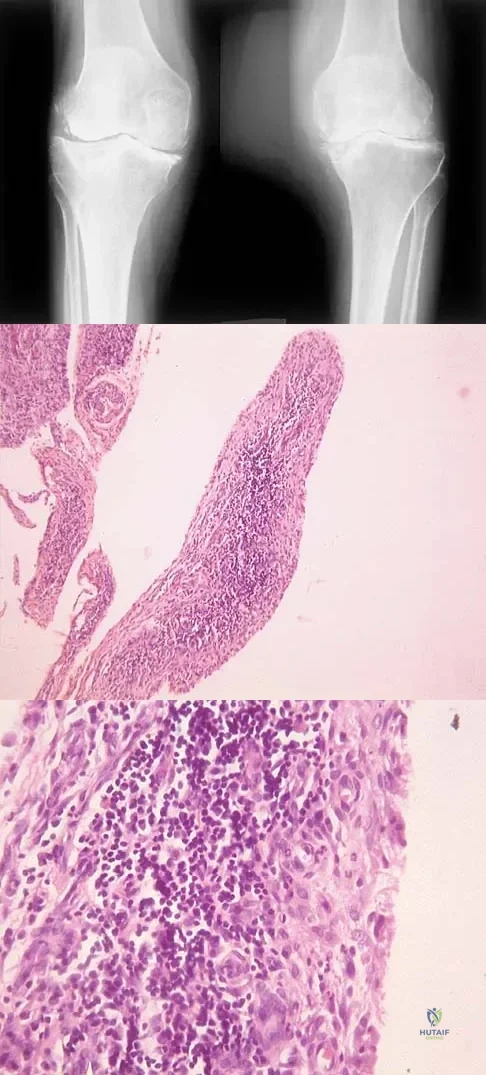

A 74-year-old woman has had acute medial right knee pain for the past 3 months. She denies any history of trauma or previous problems. Coronal and sagittal MRI scans are shown in Figures 11a and 11b. What is the most likely diagnosis?

Spontaneous osteonecrosis of the medial femoral condyle is seen in the MRI scans, and is most common in women older than age 60 years. Although usually present in the weight-bearing portion of the medial femoral condyle, spontaneous osteonecrosis has also been described involving the lateral femoral condyle and patella. Most patients are seen postcollapse, and the treatment of choice is arthroplasty. Optimal treatment in precollapse stages is controversial. Kidwai AS, Hemphill SD, Griffiths HJ: Spontaneous osteonecrosis of the knee reclassified as insufficiency fracture. Orthopedics 2005;28:236,333-336. Soucacos PN, Xenakis TH, Beris AE, et al: Idiopathic osteonecrosis of the medial femoral condyle: Classification and treatment. Clin Orthop 1997;341:82-89.